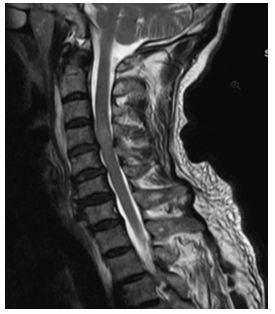

Typically, when spinal injuries involve the spinal cord, they can manifest as various degrees of signal changes. MRI can not only observe the morphological changes of acute SCI but can also precisely determine the degree of SCI based on changes in the spinal cord signal. Moreover, it can detect occult fractures and spinal cord edema, which significantly guides the formulation of treatment plans and the determination of prognosis. The MRI manifestations of SCI vary according to different lesion presentations. We consulted relevant literature on the MRI of SCI [20-22] and sought advice from professional spinal surgeons regarding its classification, finding two main types: one is based on the cause of injury, using cervical SCI as an example, which can be divided into Types I-IV, as shown in Figure 1 and Table 1; another classification method is based on the pathological changes in the spinal cord tissue, mainly divided into hemorrhage, edema, mixed type, etc., as shown in Table 2. From a medical professional perspective, the cause of injury in the first classification ultimately leads to pathological changes in the spinal cord that follow. For instance, cystic changes and glial scar formation, such types of pathological changes, usually occur during the recovery period, with early manifestations primarily being hemorrhage, edema, and mixed type. Therefore, this paper mainly uses the second classification method to detect the types of signal abnormalities in MRI and summarizes the characteristics of signal changes in SCI on MRI as shown in Table 2.

Figure 1. Imaging classification of acute cervical SCI (based on cause of injury)

Cervical spondylotic myelopathy, multi-segmental spinal canal stenosis, long-term compression of the spinal cord, MRI indicates local edema with high signal, significant behind the C5 vertebra. |

||

|

3 |

Cervical conus canal stenosis, C4/5, C5/6 disc herniation, high signal edema behind the 4th cervical vertebra in the spinal cord. |

After processing 500 images from the test set through the trained network models, the models sequentially predict and output visualization images, as shown in Figure 9, which includes some visualization results of edematous and lumbar disc herniation. Each image contains bounding boxes around the target area, along with the corresponding classification name and predicted probability value. These appropriately sized bounding boxes and predicted probabilities directly reflect the credibility of the disease. In Figure 9 below, representing a subset of the prediction set results, the credibility of SCI signals and the corresponding bounding boxes can be clearly seen, showing the location of the SCI signals within the bounding boxes and their corresponding credibility. This presentation of visualization results allows for direct observation of the predictive effectiveness of the images.